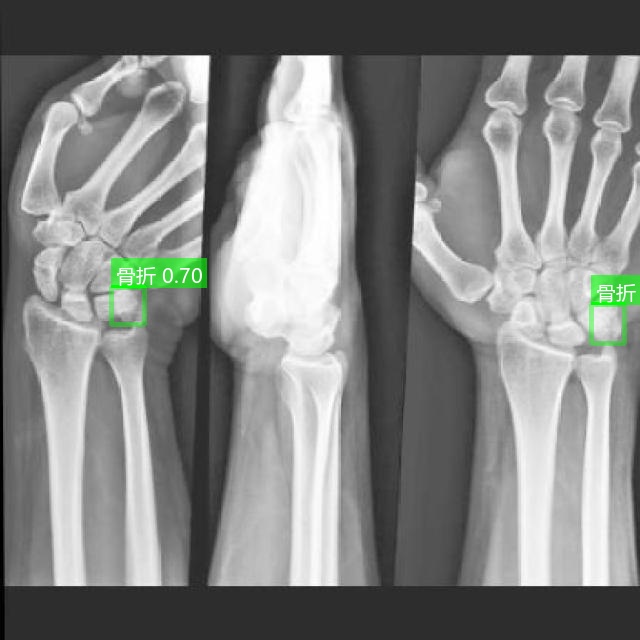

针对上述问题,本文设计并实现了一套 基于 YOLO 算法的 X 光骨折检测系统。该系统不仅能够对单张 X 光图片进行骨折检测,还支持视频逐帧检测、文件夹批量检测以及摄像头实时检测,并提供直观的可视化界面,方便医护人员快速查看和分析结果。系统同时集成登录与个人中心管理、检测结果导出、语音播报提醒等功能,提升可用性与交互体验。为进一步满足不同应用场景需求,系统还提供无界面脚本检测模式,便于在服务器或嵌入式设备中稳定运行。此外,配套的训练脚本支持用户基于自有数据训练定制化模型,涵盖数据加载、训练过程监控及结果可视化(如 F1 曲线、混淆矩阵等),形成从数据准备到模型应用的一体化解决方案。

2.5 多模态检测展示

系统支持图片、视频及摄像头实时画面的目标检测。识别结果将在画面中标注显示,并在下方列表中逐项列出。点击具体目标可查看其类别、置信度及位置坐标等详细信息。